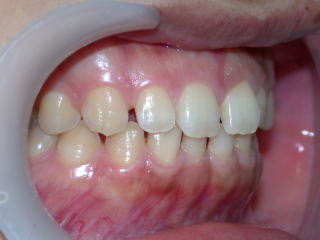

平成26年8月8日